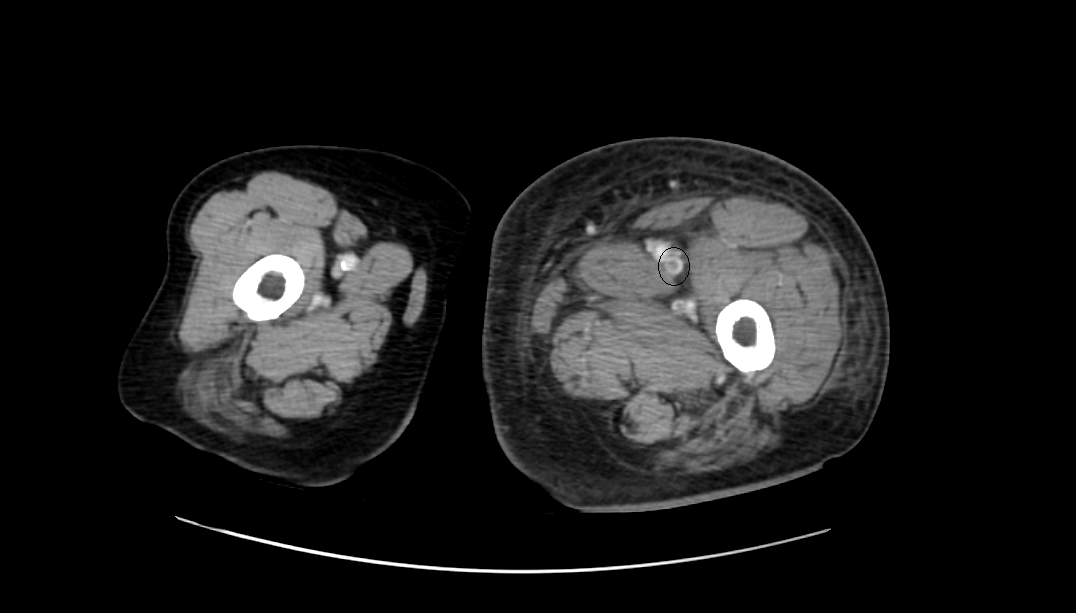

영상은 머리에 가까운 복부에서 다리 쪽으로 가는 순서로 나열하였다.

CT영상을 보면 좌측 장골정맥과 우측 장골동맥이 교차하는 지점에서부터 다리 말단 쪽으로 내려가며, 총장골정맥-외장골정맥-총대퇴정맥-표대대퇴정맥-오금정맥-경골정맥까지 혈전이 차있는 모습을 확인할 수 있었다.

Acute DVT, left CIV, EIV, IIV, CFV, SFV, popliteal and crural veins with compression of left CIV between vertebra and right CIA, c/w acute DVT with May Thurner syndrome.